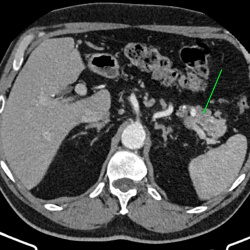

Здравствуйте, подскажите пациент 60 лет, особо жалоб нет, на узи было изменения в печени, в хвосте поджелудочной железы отмечаются немного гиподенсивные изменения может ли это быть раком? на МРТ...